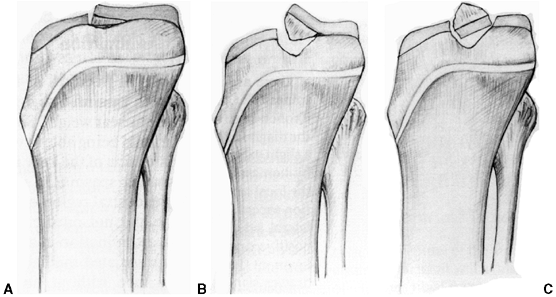

Figure 32.3 Patellofemoral biomechanics. A:

The Q angle relates the direction of pull of the quadriceps mechanism to that of the patellar tendon. These are the two most powerful forces exerted on the patella. Their vector sum is directed laterally. B: There are additional soft tissue forces applied to the patella. C: The laterally directed net vector is opposed by the patellofemoral articulation. If the groove is shallow, there is less potential resistance to horizontal translation than in knees with a deeper femoral groove. The dysplastic patellofemoral articulation results in less resistance to lateral translation, and therefore greater sheer forces on the articular surface. |

advocated as well. If the individual is a skeletally mature youth, the

tibial tubercle is osteotomized and shifted medially without distal

transfer (Elmslie-Trillat procedure) (59) (Fig. 32.5 A,B). A modification of the Elmslie-Trillat procedure is the Fulkerson procedure (60),

in which a more generous osteotomy of the anterior tibial tubercle is

performed and the tubercle transferred anteriorly and medially (Fig. 32.5C).

This procedure is primarily reserved for patellofemoral pain in adults

and is not recommended for instability in adolescents or young adults.

Figure 32.5 A, B: The Elmslie-Trillat technique shifts the tibial tubercle medially. The tubercle stays in the same plane. C:

The Fulkerson modification involves an oblique cut that results in anterior translation as the tubercle is moved medially. This reduces the patellofemoral contact forces while shifting the pull of the patella medially. |